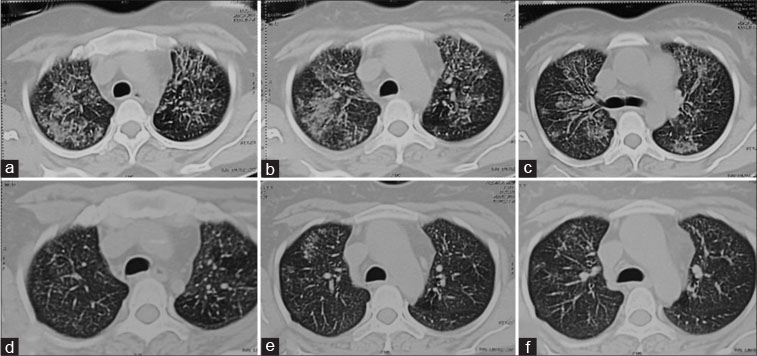

| Figure 2 Pretreatment computed tomography scan - axial high resolution sections in lung windows show diffuse perihilar groung glass haziness and peribronchial thickening in bilateral mid zones (a-c). The same patient’s posttreatment corresponding high resolution sections show marked resolution of the interstitial pneumonitis (d-f)